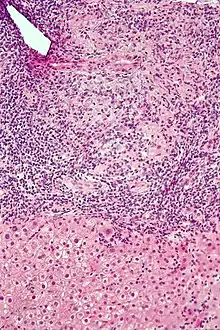

Micrograph of PBC showing bile duct inflammation and injury, H&E stain

On microscopic examination of liver biopsy specimens, PBC is characterized by chronic, nonsuppurative inflammation, which surrounds and destroys interlobular and septal bile ducts. These histopathologic findings in primary biliary cholangitis include:[32]

• Inflammation of the bile ducts, characterized by intraepithelial lymphocytes

• Periductal epithelioid granulomas.

• Proliferation of bile ductules

• Fibrosis (scarring)